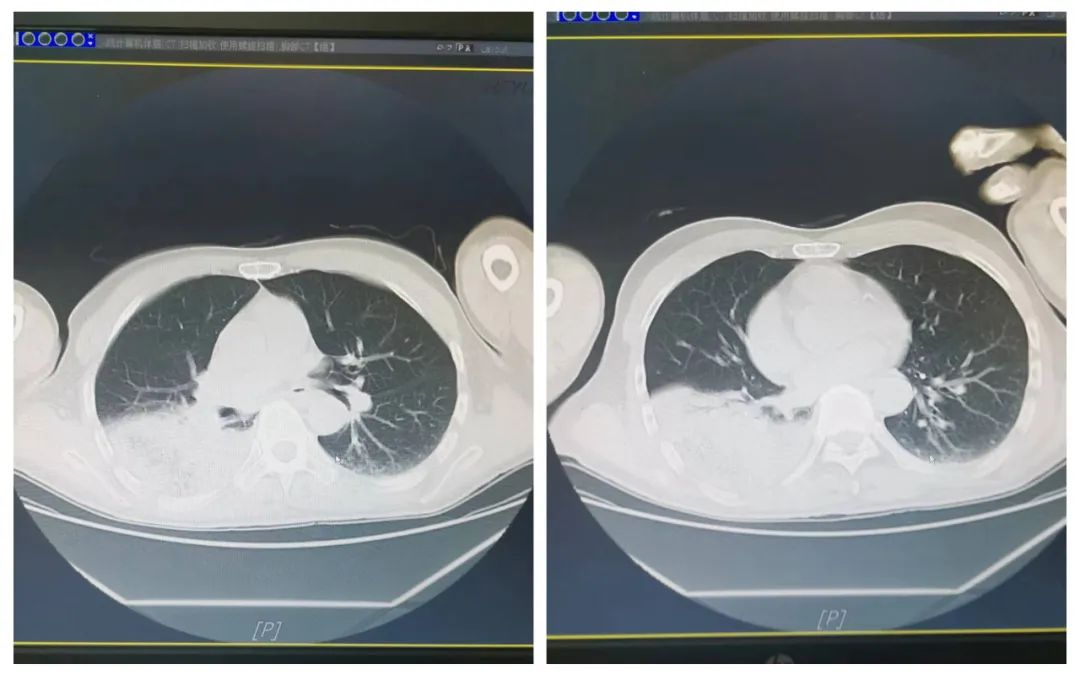

患者胸部CT示右下肺肺炎